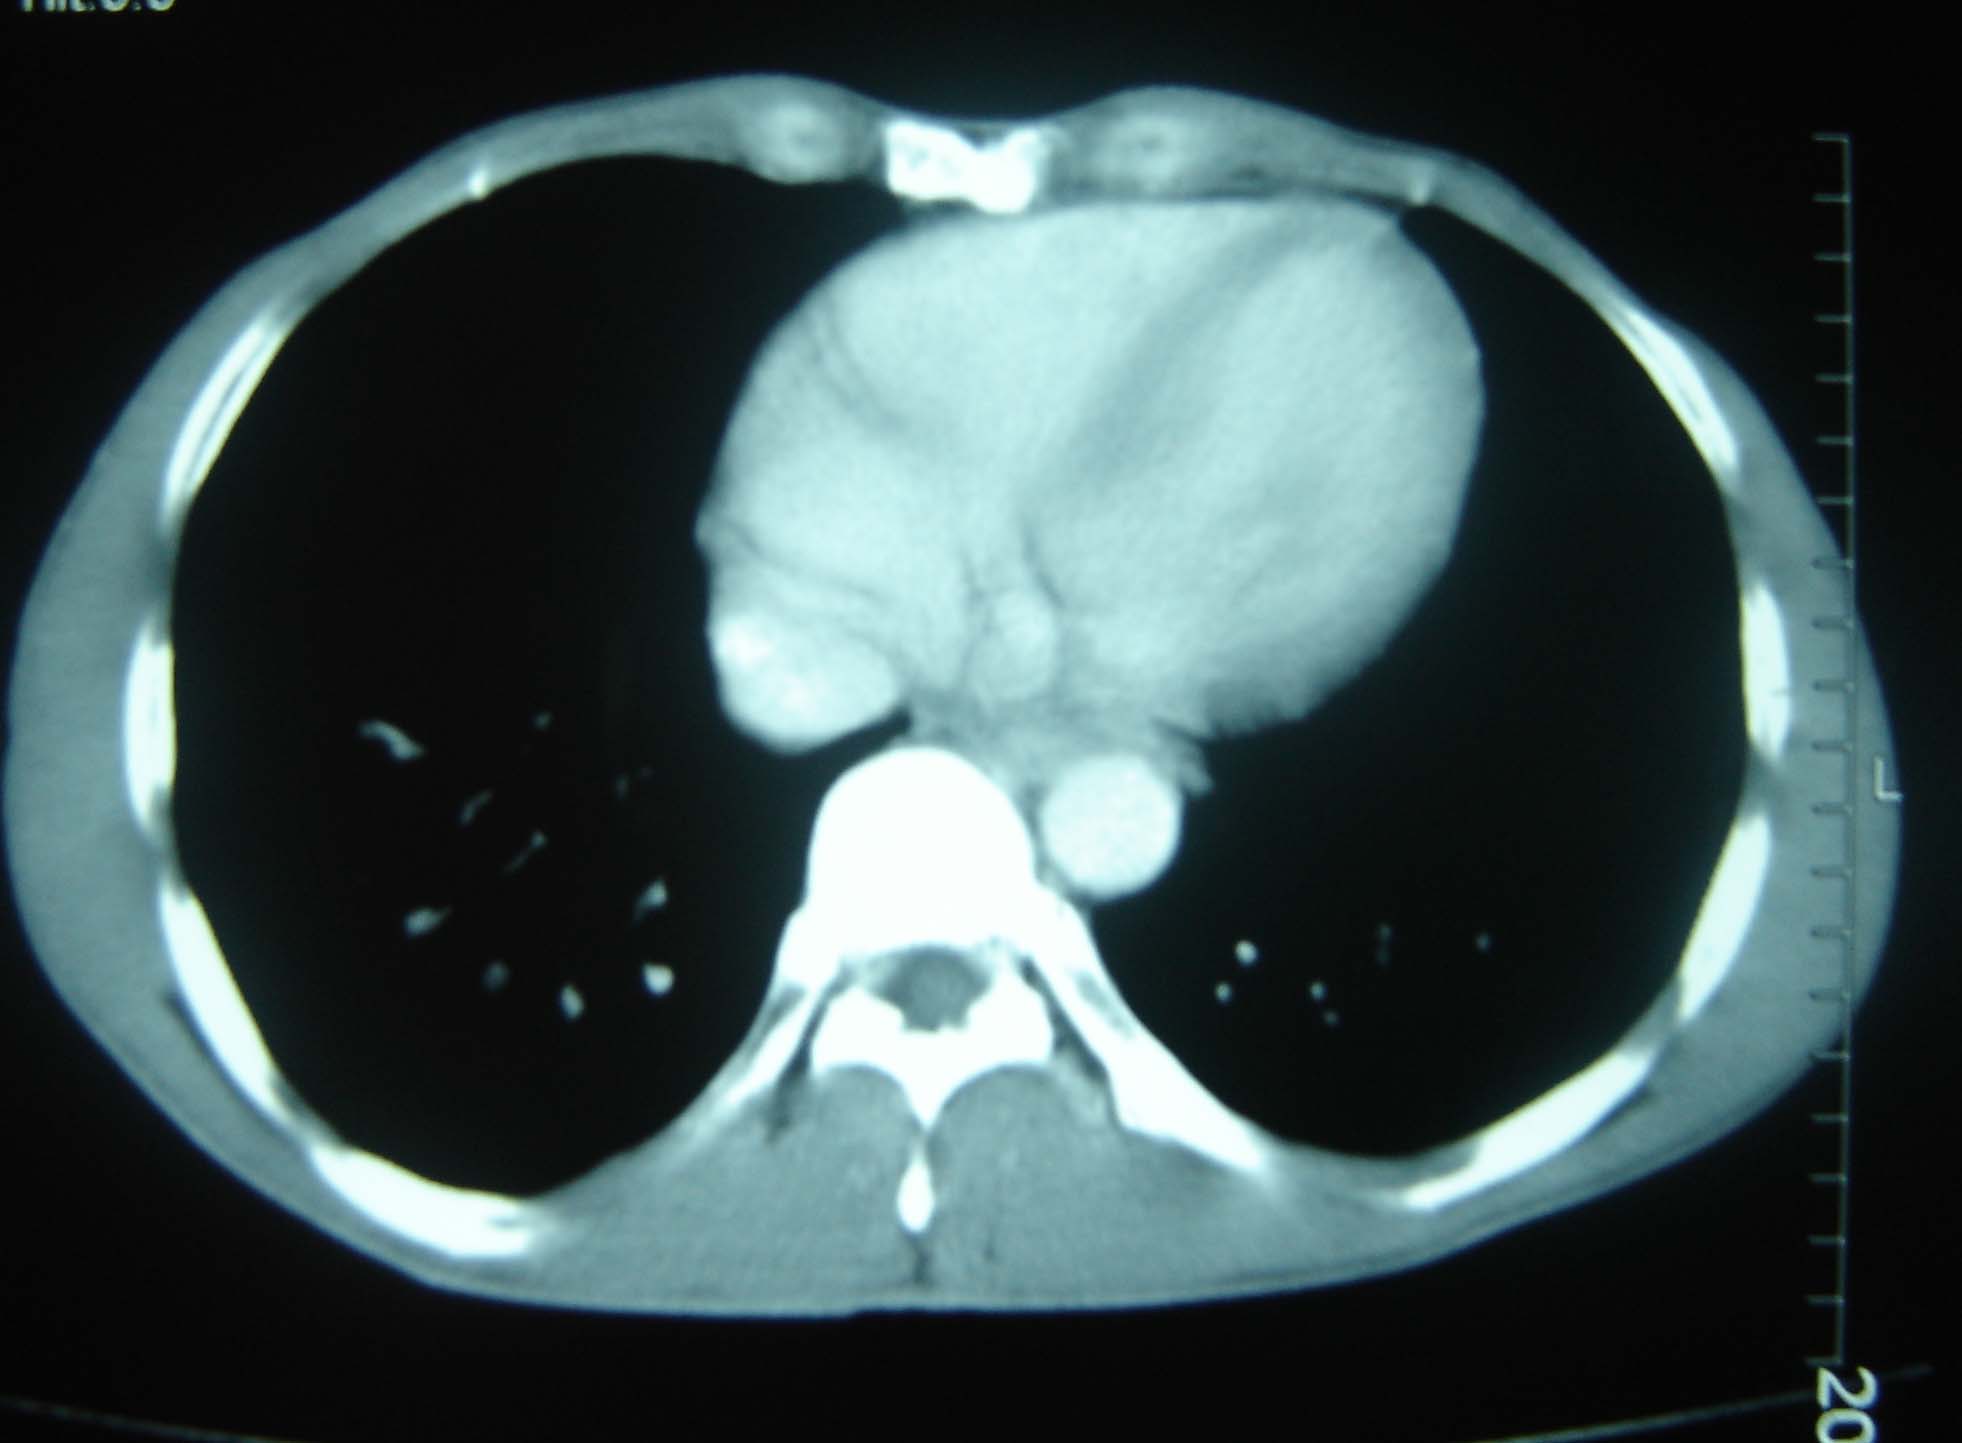

标题: CT25321:两肺多发结节 请会诊 [打印本页]

男 、43岁,咳嗽胸痛,装修工,平时接触粉尘较多,有吸烟史10多年,纤维支气管镜检查未发现异常,胃镜、腹部b超检查亦未发现异常,颈部淋巴结活检未发现肿瘤细胞。

1)考虑双肺及胸膜多发性转移瘤。2)肺气肿。